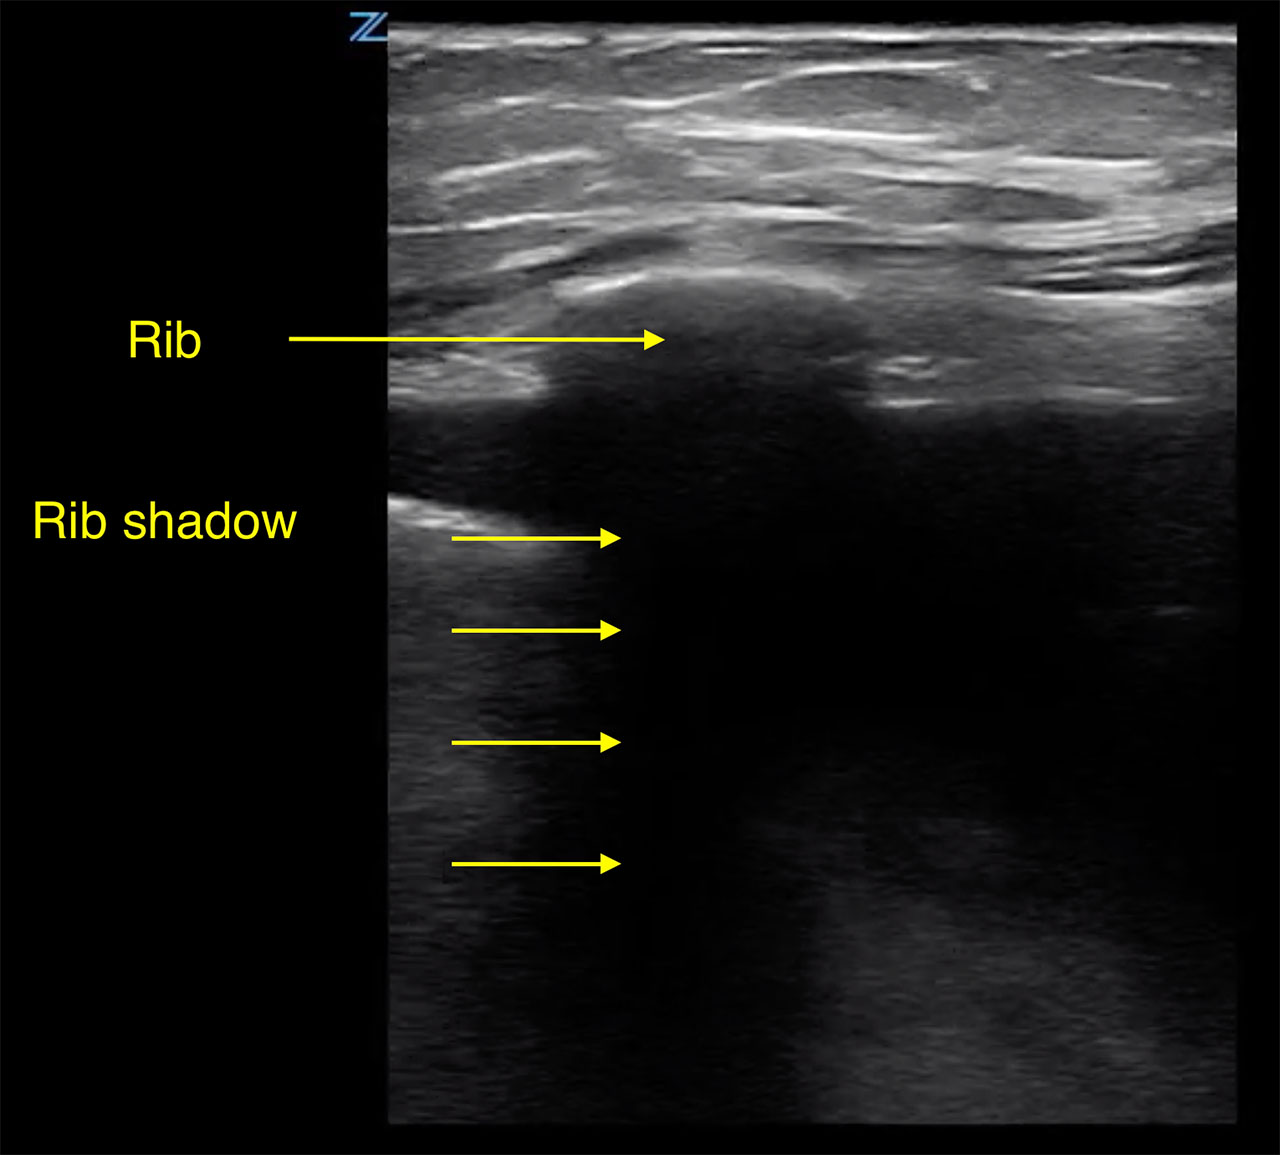

- In order to visualize an effusion, the ultrasound beam will first image the chest wall, pleural line and the ribs.

- The edge of bone is echogenic and gives off a characteristic shadowing. (Fig. 4)

- Figure 4. Pleural effusion with rib shadow. The transducer is placed perpendicular to the axis of the rib